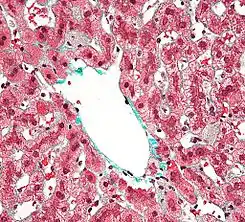

Biopsia hepática en la que se observan células de Kupffer centrolobulares, con un citoplasma granular de color gris, en una lesión hepática teñida con tricrómico de Masson.